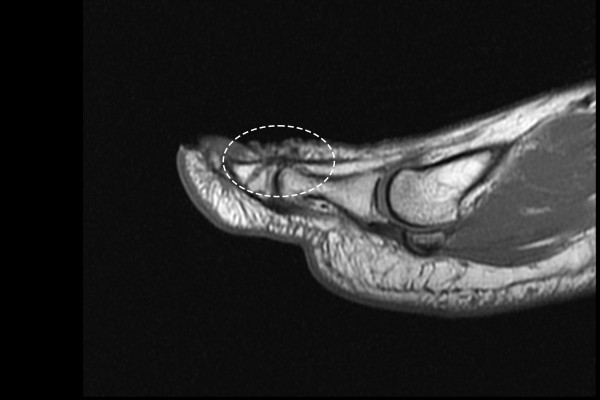

아래에 힘줄을 보면 검은색 힘줄이 잘 연결되어있으나 위에 장무지신전건을 보시면 파란 점선처럼

연결되어있어야 할 힘줄이 끊어져있는것이 확인됩니다.

b1d6a7ed823268faf8290a31a2d8a8bb_1765956477_0314.jpg

수술이 필요한 상태로 장무지신전건 재부착술(Lt. foot 1st EHL re-attachment c suture anchor)을

시행하였습니다.

수술 사진을 보시면 하얀색 힘줄이 떨어져서 빈공간이 확인됩니다.